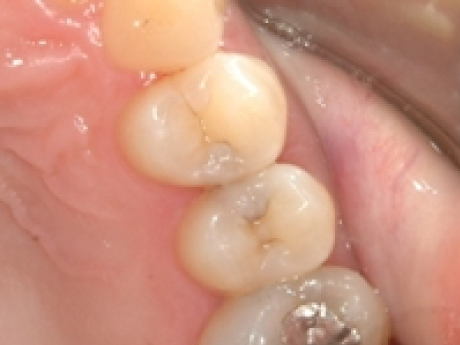

case4